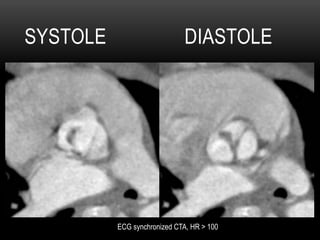

•  5 yo male with murmur, FTT

SYSTOLE DIASTOLE

ECG synchronized CTA, HR > 100